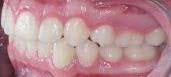

En las fotografías intraorales (Figura 3) observamos una clase II molar bilateral, clase II canina derecha, clase III canina izquierda, apiñamiento severo superior y moderado inferior, presencia de mordida abierta anterior y posterior a nivel de premolares (Figura 4), forma de arco triangular en la arcada superior y forma de arco oval en inferior, ausencia del OD 46 y presencia de un diente supernumerario.

Figura 2. Fotografías extraorales frente y perfil. Figura 3. Fotografías de frente, lateral derecha, lateral izquierda.